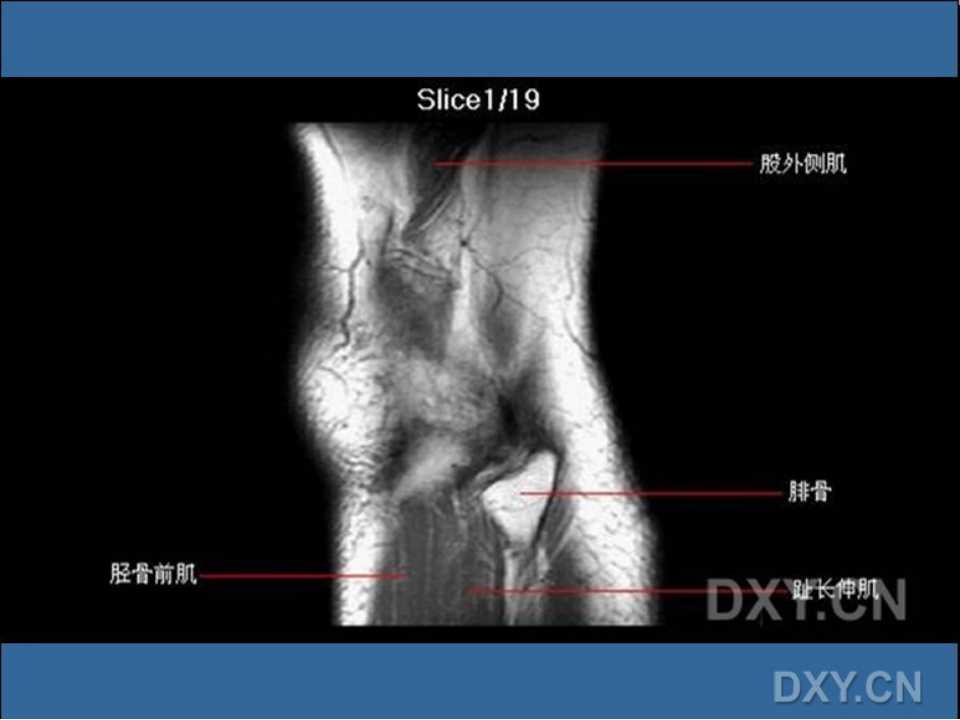

本 PPT 清晰展示踝关节正常 MRI 图像。 2016.07.26